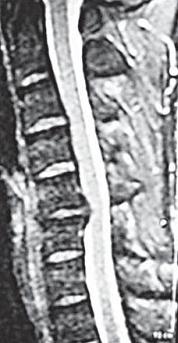

МРТ № 19

На МРТ № 19 наблюдается дорсальная грыжа межпозвонкового диска шейного отдела позвоночника в сегменте СV-СVI с компрессией спинного мозга